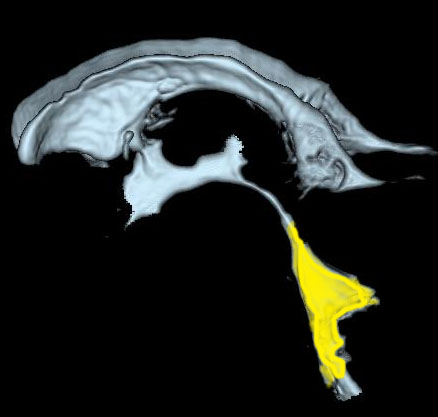

後頭部に近い所にあります。黄色が第4脳室で,髄液の通り道(出口)です。

前方には脳幹部,後ろは小脳虫部です 。

上は細い中脳水道につながって,下はマジャンディー孔と左右のルシュカ孔に開いています。